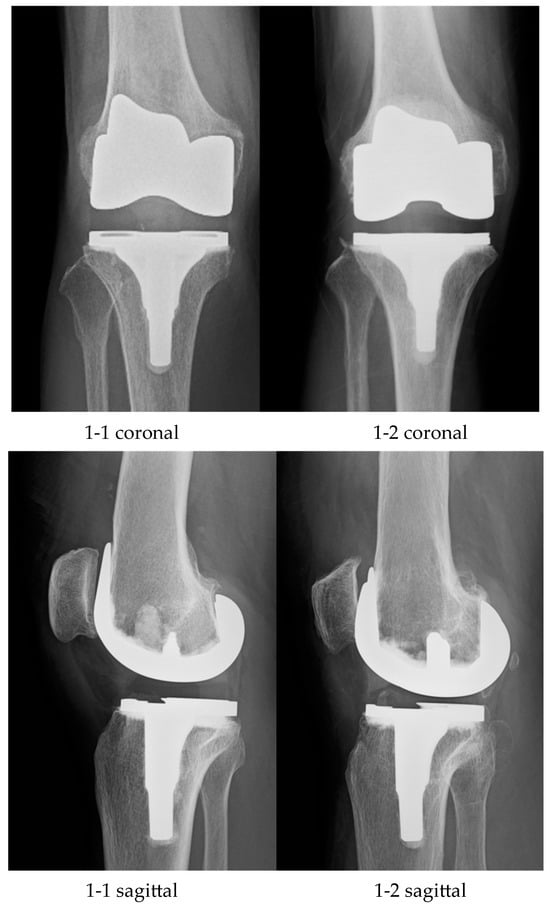

2.1. Surgery and Postoperative Rehabilitation